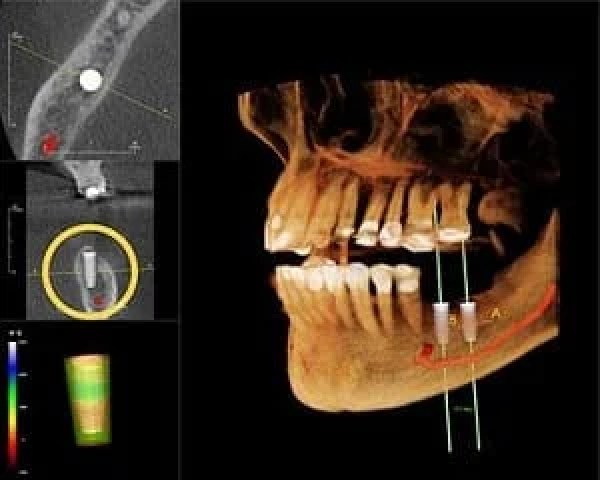

Improved Implant Placement With 3D Images

When the jaw is ready, Dr. Rubina carefully implants titanium posts, which function as tooth roots. Critical to the success of implants is their strategic placement, and Bella Vista Smiles uses 3D scans that reveal detailed images of your unique oral structure. A predetermined plan is programmed into a robotic cylinder for precise and optimal implant placement.